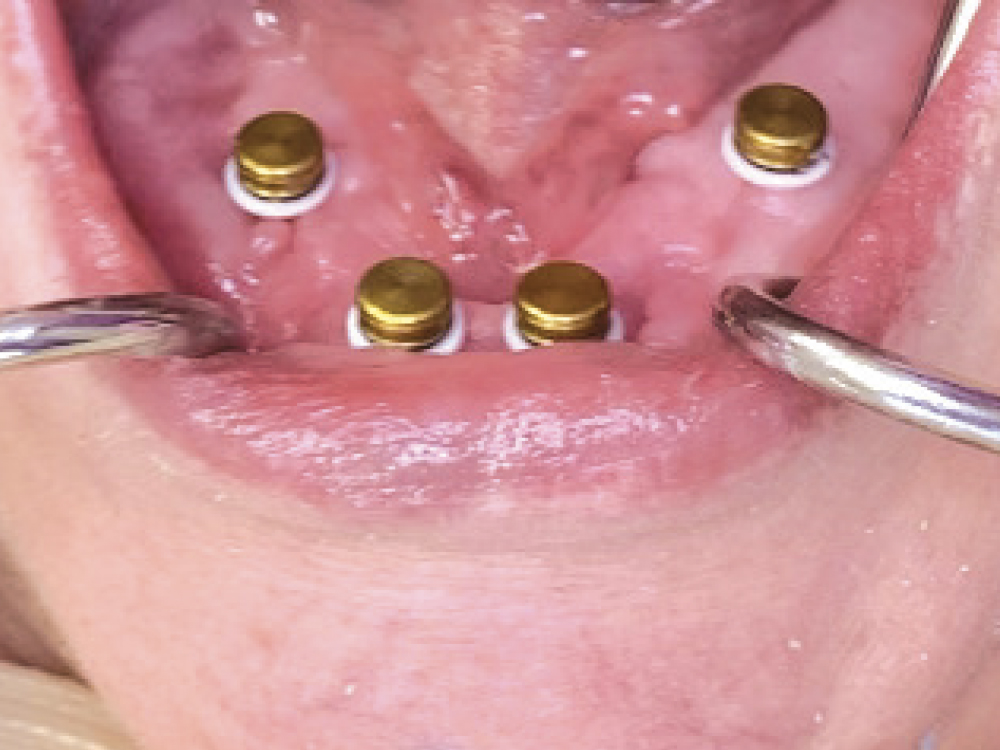

Metal housings with black attachments were snapped onto all the Locator Abutments. White blockout spacers were positioned apical to the housings.

Figure 8: Metal housings with black attachments were snapped onto all the Locator Abutments. White blockout spacers were positioned apical to the housings.

Locator Fixed Attachments are available in three different retention levels and are identified by different colors: green (for four-unit cases), blue (for five-or-more-unit cases mid-arch), and tan (for five-or-more-unit cases in the anterior or posterior). Metal housings with black processing attachments were snapped on the abutments according to the selection recommendations for a case with only four implants. In this case with four abutments, all the implant sites received metal housings containing green attachments.

Green Locator Fixed Attachments are used in all sites for four-implant cases.

igure 5: Green Locator Fixed Attachments are used in all sites for four-implant cases.